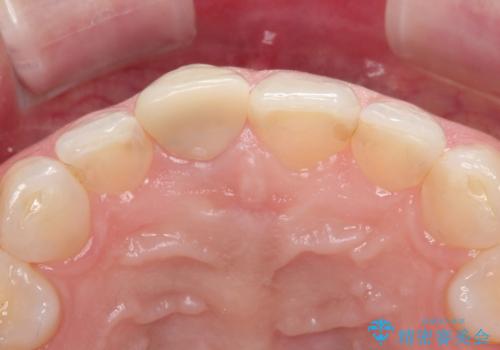

10年前に根管治療を他院で行っており、根尖性歯周炎の予防のため根管治療から行いました。被せものはオールセラミッククラウンで治療を行いました。

10年前にラバーダムシート無しに根管治療を行っており、現在、症状は出ていませんが、根尖性歯周炎の予防のため根管治療から行いました。ホームホワイトニングを2週間行って頂き、その後、オールセラミッククラウンで治療を行っています。

※ファイバーコアとは、根管治療後、歯に立てる土台の事です。金属の土台と比べ歯根破折のリスクが低く、白いのが特徴です。

※被せものでは歯と被せものの適合がとても大切になります。適合が悪い被せもの(歯と被せものの間に隙間がある)を入れるとそこに汚れが溜り虫歯の原因となります。当院では精度が高い被せものを追求するため、サージテル(拡大鏡)や型取りの材料にシリコン材を使用しています。